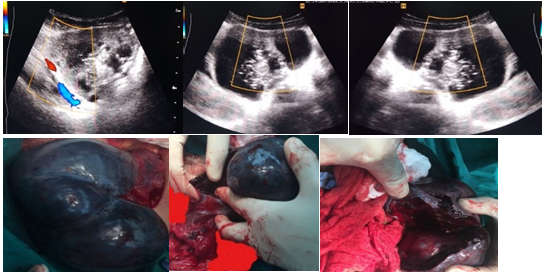

Case 7: Severe discomfort and irregular menstruation plagued a 48-year-old woman. Ultrasound indicated the proper bulk, which had both liquid and solid material (8cm). The ovary was removed after a laparotomy discovered a cyst adenoma (Figure 7).

Figure 7 Ultrasound imaging of the right mass, which contains both liquid and solid material. The ovary on the opposite side is typical, having a multifollicular appearance.

Case 8: The patient, a 39-year-old woman, was in excruciating agony and vomiting. Ultrasound of the pelvis and vaginal cavity revealed a complicated mass (>5cm). Doppler showed a negative result. A laparotomy revealed a hemorrhagic cyst in torsion (Figure 8). The diagnosis was confirmed by histology.

Figure 8 Ultrasound of the pelvis and vaginal region revealed a complicated mass with a solid component papillary appearance and a negative result. Doppler.